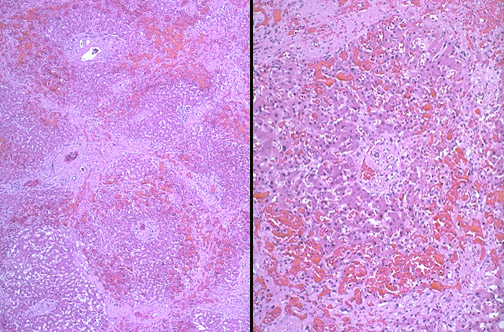

| If chronic hepatic passive congestion continues for a long time, a condition called "cardiac cirrhosis" may develop in which there is fibrosis bridging between central zonal regions, as shown below, so that the portal tracts appear to be in the center of the reorganized lobule. This process is best termed "cardiac sclerosis" because, unlike a true cirrhosis, there is minimal nodular regeneration. |